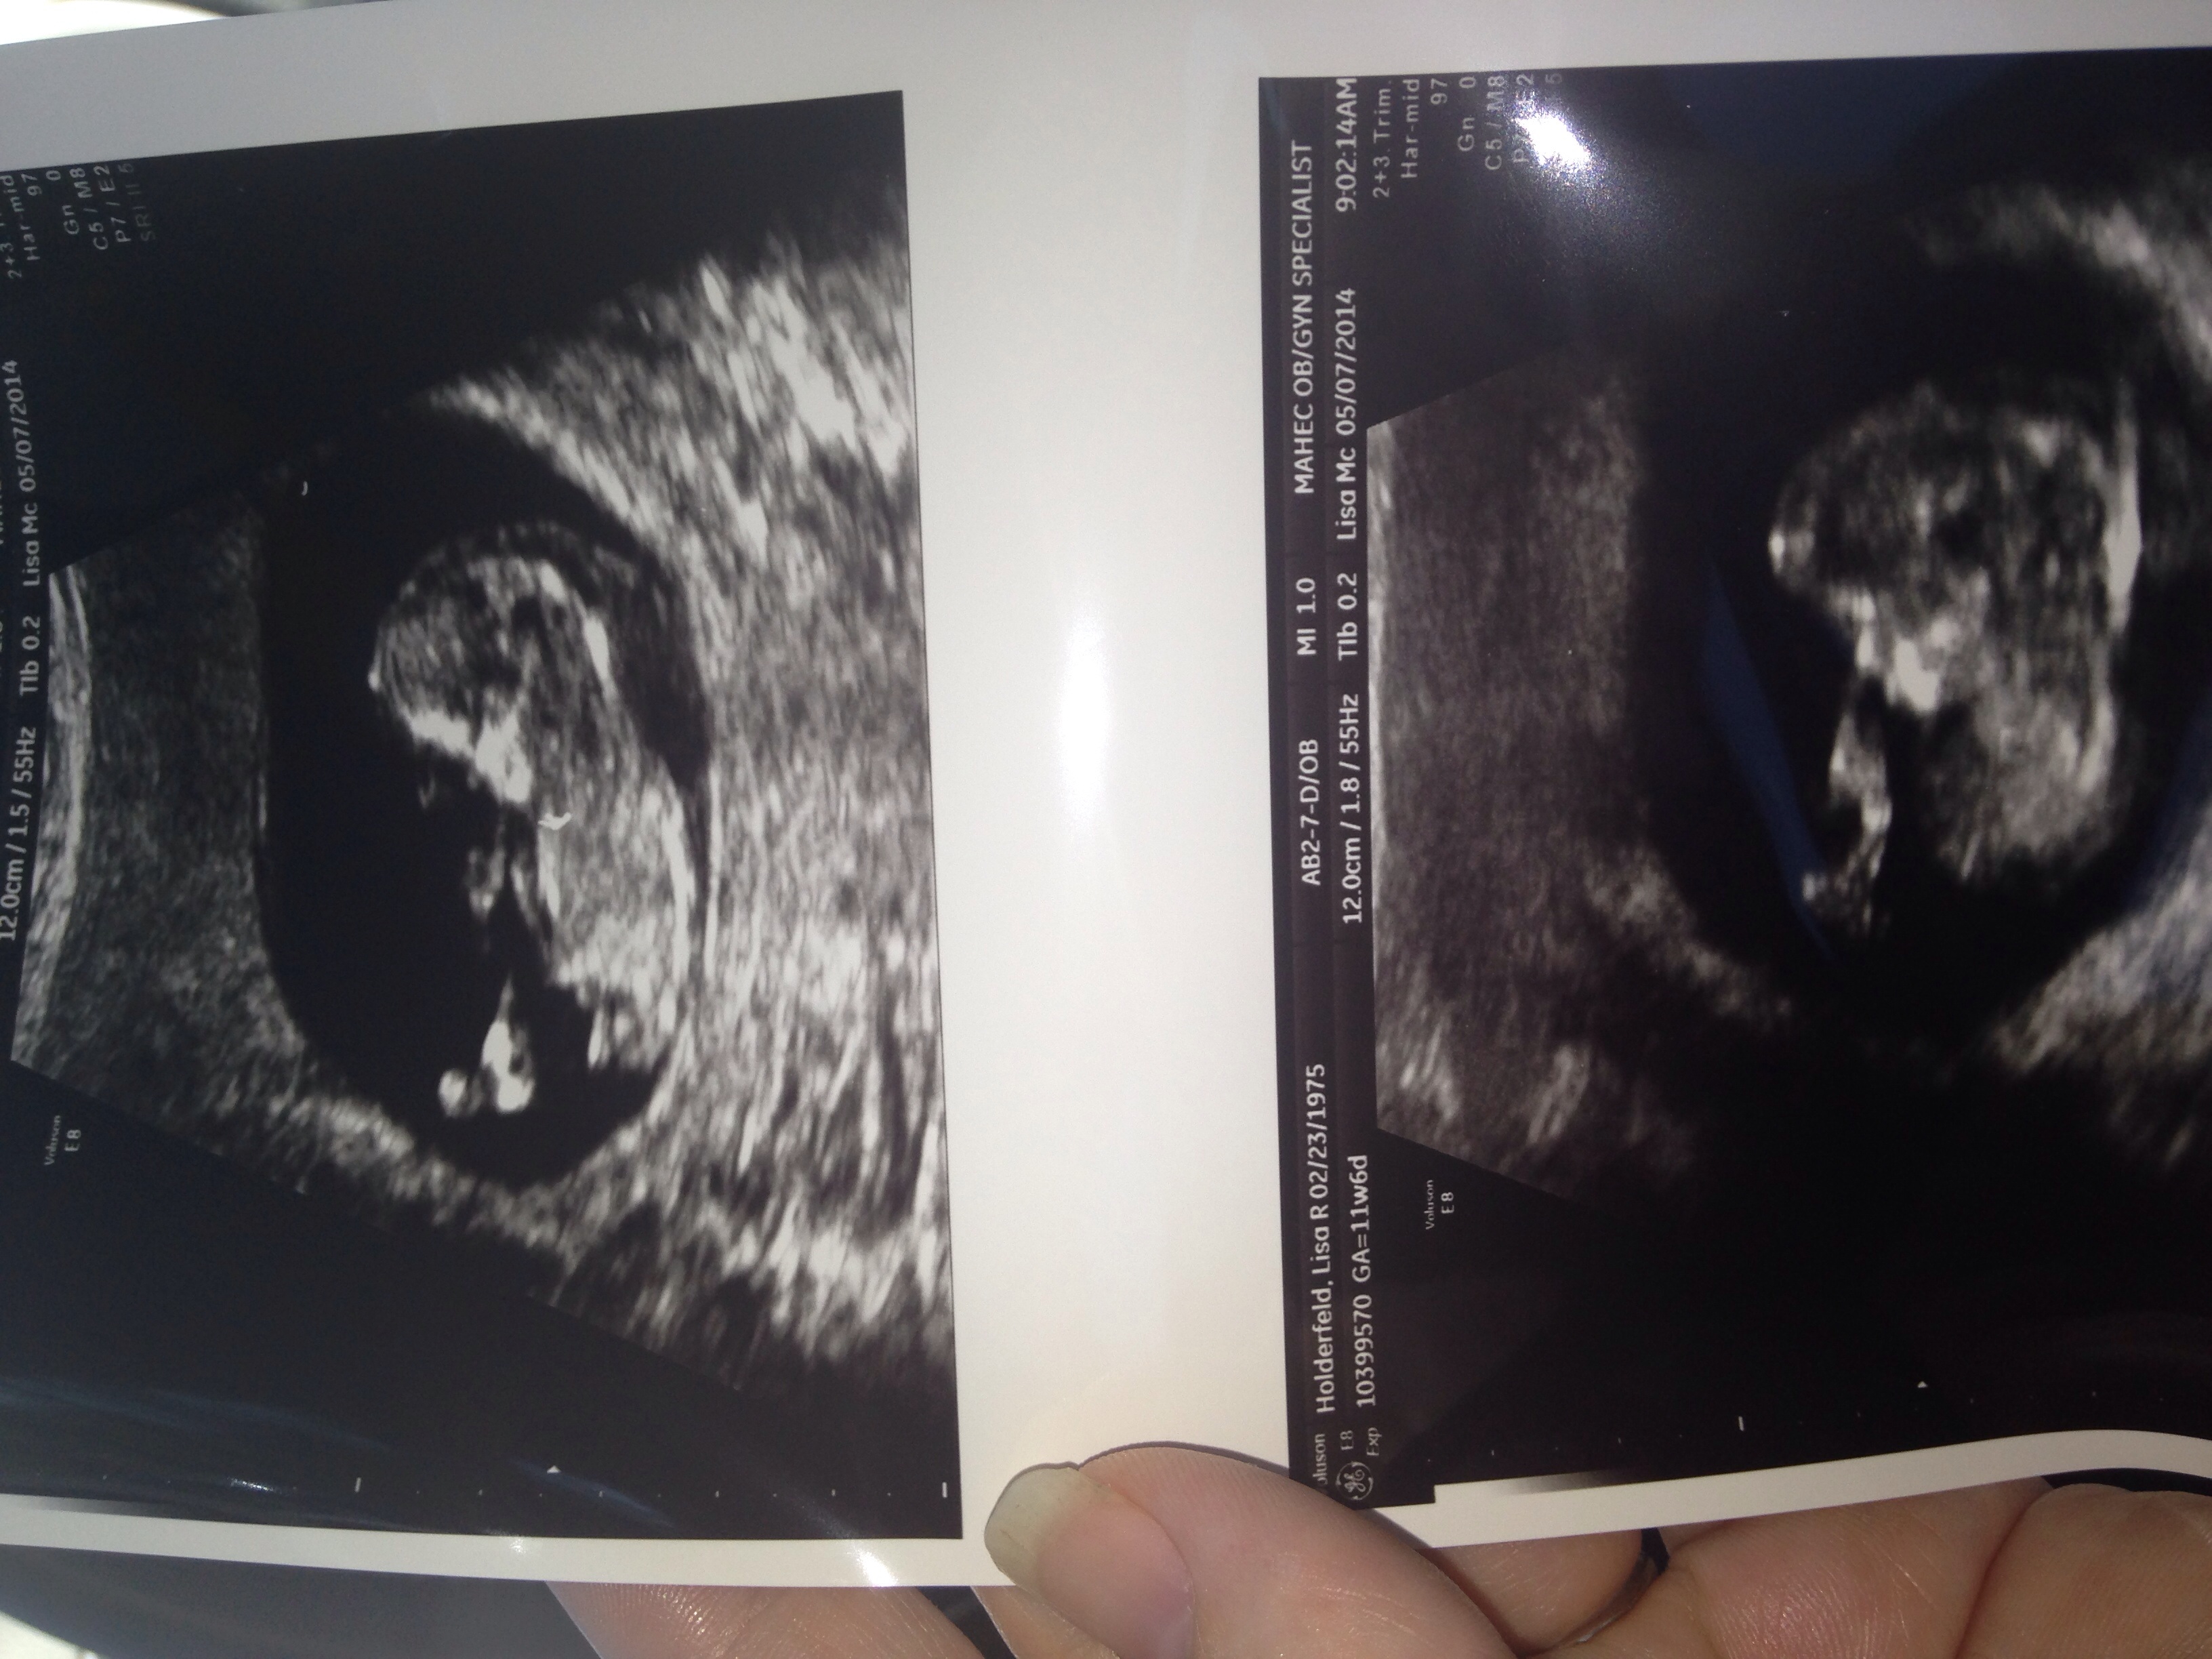

Here's the picture. They tried to find one that had a profile. You can see the halo on the bottom pic. I know my info is on here but it's fine. Such a sweet nose.

Could not do cvs. The fluid is all around baby, like a halo, under the chin, and seeping in abdomen. It's like the baby is wearing a spacesuit. The outcome will Not be good. The baby's belly is already swollen. The MFM Dr has been amazing as well as my midwife.Tomorrow is Emma Claire's birthday so we will celebrate this with smiles. With seeing this big of a cystic hygroma in this gestation of pregnancy, the baby will develop hydrops and/or pass before birth, the inevitable will happen. At this point waiting for this seems cruel and unfair to the sweet baby. Nothing seems to make much sense. I'm hoping the decisions we've made and continue to make will be the right ones and we can find peace within.

Since I'm Not having contractions the placenta is not in a good spot so may not be able to do cvs. We looked at baby and oh she's so precious. I really think it's a girl. She was stretching her legs. The hygroma is big. Very big. From the top of the head down to the butt. Plus her abdomen is swollen with fluid. Edema. Hygromas this large don't end well. The increase fluids on body, lungs and heart can eventually cause the baby to pass. I'm waiting to see if the contractions -Braxton hicks to me, push the placenta up. Also no hydrops.